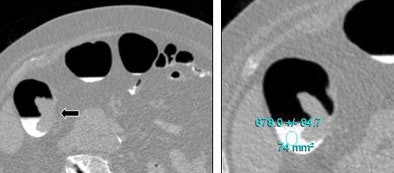

| Above, tagged fluid surrounds a malignant tumor (arrow). The tagged fluid has a density of 678 HU. Images courtesy of Dr. Philippe Lefere. |

The biggest difference was seen in group 3, which received a final dose of 25 mL of 4% barium solution on the morning of the exam. Most parameters were similar to those in Group 1, except that just 3.3% of segments had untagged fluid, representing a major improvement in fluid tagging.